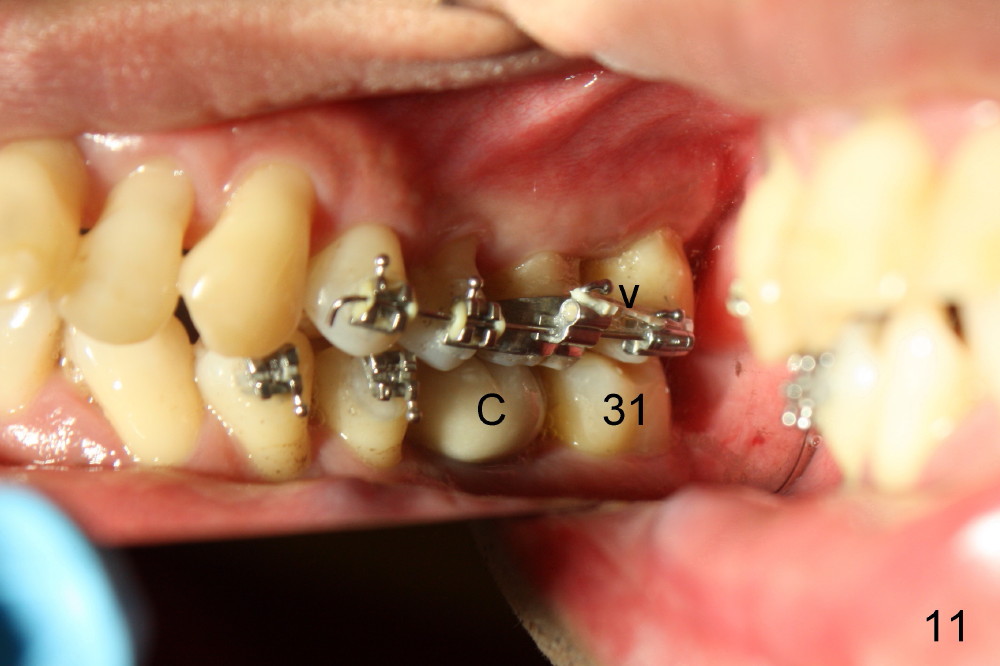

In 7 months, the right molar occlusion changes to Class I with normal overjet (Fig.8 mirror view). Class I posterior occlusion correction is evidenced by a gap between the teeth #30 and 31 (Fig.9 arrowheads) due to elastic retraction. There is no tension (bending) of wire between the teeth #2 and 3 in the final stage (Fig.10 arrowhead, as compared to Fig.7). A porcelain crown is subsequently cemented to the implant/abutment complex with occlusal equilibrium (Fig.11(mirror image) C). The remaining brackets and band are removed. Power chains in Fig.11 (arrowhead) were used to correct the rotation of the tooth #2 (Fig.10, bracket in the tooth was not well placed).